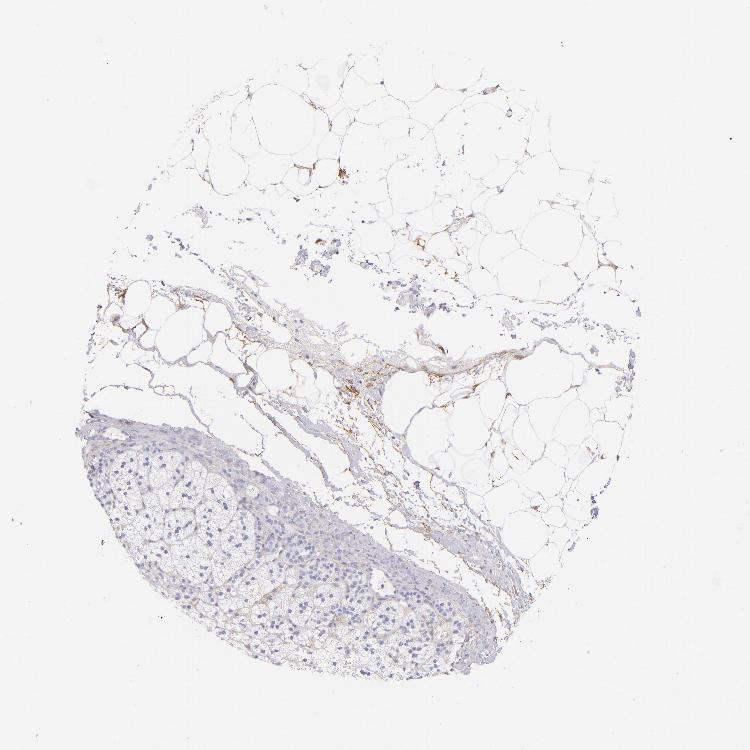

ADRENAL GLAND - Antibody stainingi

Antibody staining in the annotated cell types in the current human tissue is reported as not detected, low, medium, or high, based on conventional immunohistochemistry profiling in selected tissues. This score is based on the combination of the staining intensity and fraction of stained cells.

Each image is clickable and will lead to virtual microscopy that enables deeper exploration of all samples and also displays staining intensity scores, fraction scores and subcellular localization as well as patient and tissue information for each sample.

Antibody HPA007234Antibody CAB002507

Glandular cells Not detectedNot detected